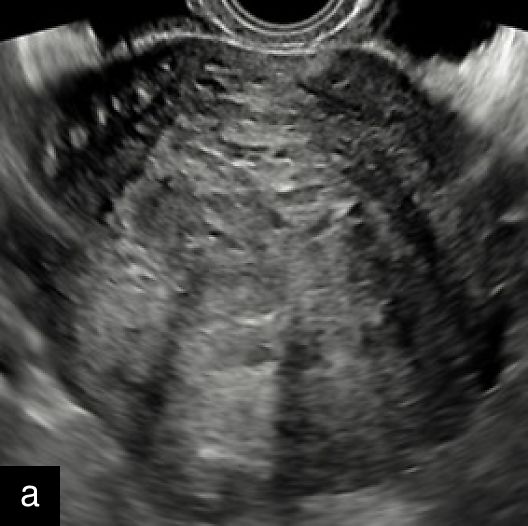

A retrospective series of 20 STUMPs further described most lesions as well-defined (85%), with non-uniform echogenicity, isoechoic (60%) or mixed echogenicity (30%) and microcystic anechoic areas (70%). No shadowing and no calcifications were reported. No calcifications or shadowing were observed, and the vascularization was predominantly poor-to-moderate (69%), with both circumferential and intralesional blood flow patterns being common (90%)28 (Figure 4).

4

Grayscale (a) and color Doppler (b) transvaginal ultrasound images of a STUMP showing a heterogeneous mass with irregular echotexture. (b) Doppler imaging highlights scattered vascularization, with a color score of 3, indicating moderate vascularity and a potentially atypical neovascularization pattern.